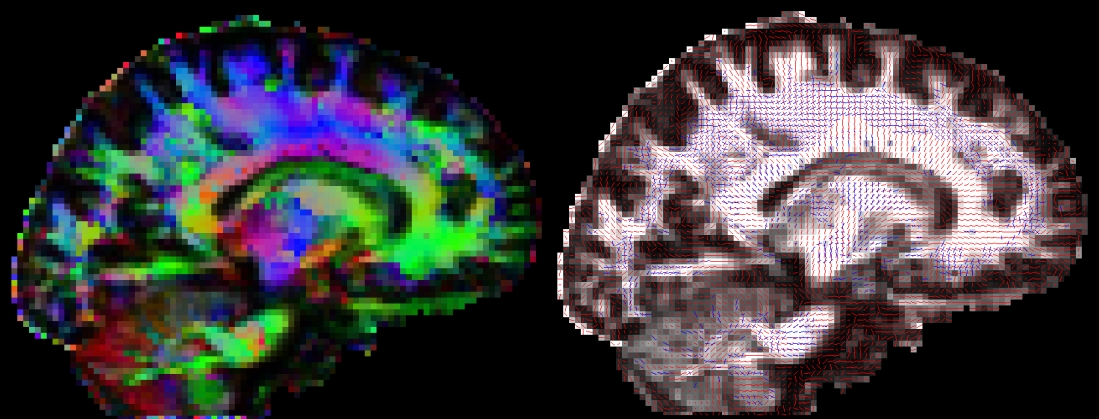

vecreg - Registration of vector images

After running dtifit or bedpostx, it is often useful to register vector data to another space. For example, one might want to represent V1 for different subjects in standard space. vecreg is a command line tool that allows to perform such registration.

Vector images cannot be registered by simply applying a transformation (as calculated by, say, FLIRT) to every voxel's coordinates. The corresponding vectors have to be reoriented accordingly (see D. Alexander 2001, IEEE-TMI 20:1131-39). vecreg performs this operation for you. The image on the right shows the effect of applying vecreg (right) to the V1 image on the left, compared to simply applying voxelwise transformation (e.g. using applyxfm4D) to the vectors (centre).

Important: vecreg does not calculate a transformation, but simply applies a given transformation to the input vector field. vecreg can apply a linear transformation calculated with FLIRT, or a non-linear transformation calculated by FNIRT.

types of input that may be used for vecreg from DTIFIT: V1,V2,V3,tensor from BEDPOSTX: dyads1, dyads2, etc.